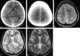

Cysticercus

Cysticercus (pl. cysticerci) is a scientific name given to the young tapeworms (larvae) belonging to the genus Taenia. [Source: Wikipedia ]